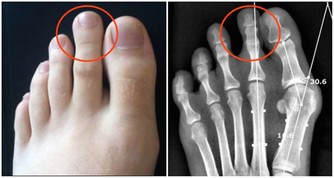

尿酸痛風的人,可以每天吃一碗莧菜湯,或像我們客家人用莧菜煮麵線,但是不要放吻仔魚。

莧菜能平衡酸鹼,你的尿酸痛風就會好。

不要吃冰的東西,不要吃香蕉,香蕉吃了痛風就發作,因為裡面有鉀離子。

莧菜補血,就是紅莧菜,又使痛風消,

所以每天用一碗面線、一把莧菜,保證不會體重增加,保證尿酸痛風全部消掉。